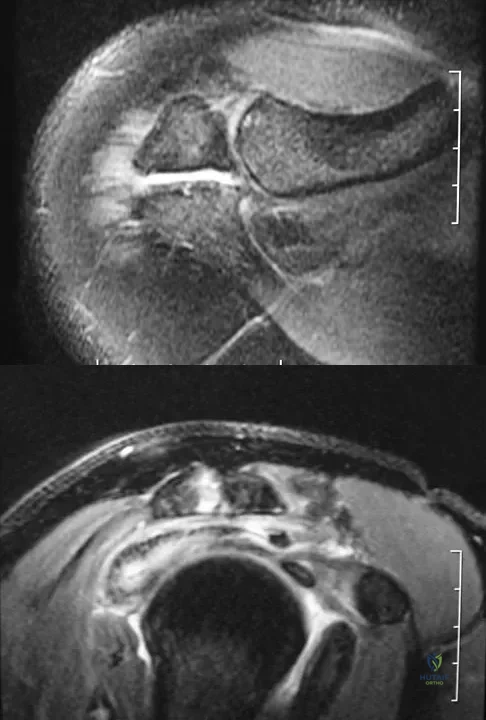

A 25-year-old tennis player has shoulder pain and weakness to external rotation. MRI scans are shown in Figures 16a and 16b. What is the most likely cause of his weakness?

Explanation